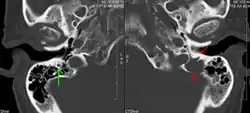

Pathological fracture of the lumbar spine due to multiple myeloma - A CT of the brain revealed a lytic lesion in the left temporal bone (right side of image), and petrous temporal bones involving the mastoid segment of the facial nerve canal. Red arrows: lesion; green arrow: normal contralateral facial nerve canal. The lesions are consistent with a myeloma deposit.